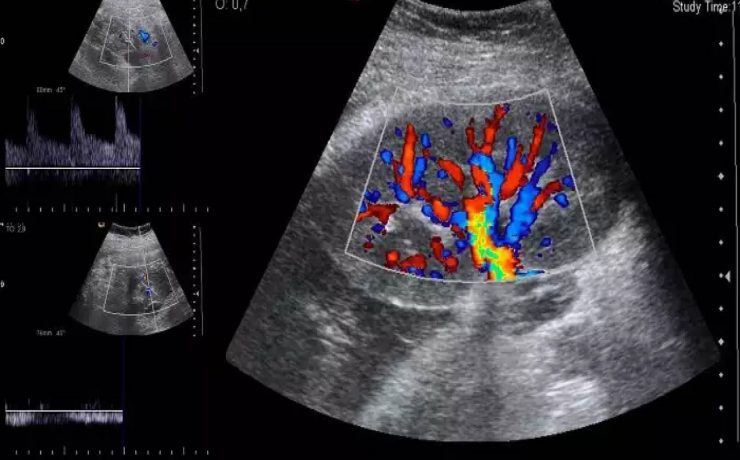

El desarrollo embrionario y fetal del riñón y de las vías urinarias es un proceso biológico extraordinariamente complejo. La formación del riñón definitivo se inicia a partir de la quinta semana de vida intrauterina y su desarrollo depende de la interacción de sus dos compartimientos tisulares; la yema ureteral que